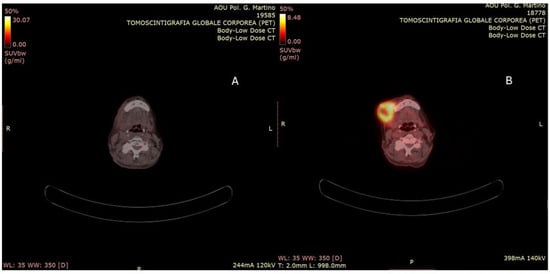

The V95 was 58 Gy for the GTV and 53 Gy for the CNV. The mean doses to the left parotid and submandibular glands were 10 Gy and 11 Gy, respectively. Mandibular V50 and V42 were 31% and 44%. The pharyngeal constrictor muscles received a mean dose of 26 Gy. Maximum doses to the spinal cord and esophagus were 30 Gy and 35 Gy, respectively. The patient completed the treatment without interruption. Ninety days after the conclusion of the treatment course, a PET-CT scan was performed, revealing a marked reduction in both the extent and intensity of radiotracer uptake when compared to the previous examination (Figure 3). From a clinical standpoint, there was clear evidence of complete resolution of the ulcerative skin lesion, with an excellent cosmetic outcome (Figure 4). Treatment-related toxicity was limited to grade 2 mucositis, which was resolved within two weeks through the administration of topical mouthwash containing an antifungal, corticosteroids, and lidocaine. At the last follow-up, 10 months after the completion of therapy, no signs of disease progression were observed.

Figure 3. (A,B) PET-TC evaluation performed 90 days after the end of treatment. (A) The complete metabolic remission of the lesion compared to the staging PET CT (B).